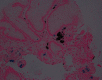

Gastric pseudomelanosis is a benign condition that has been characterized by pigment deposition within subepithelial macrophages inside the stomach wall. Occurrence of the condition is rare, with pseudomelanosis occurring more often within the duodenal mucosa. Few cases have reported pseudomelanosis within the gastric mucosa. We report a case of an 86-year-old female who presented with worsening iron deficiency anemia concerning for gastrointestinal bleeding. Her endoscopic evaluation was remarkable for a speckled pattern of dark pigmentation within the stomach, confirmed to be pseudomelanosis by histologic evaluation with pigment showing positive staining for iron.